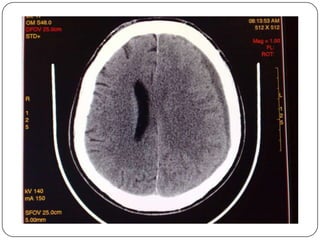

Hematoma Subdural  Sangreentre la dura y la aracnoides  No hay relacion con fracturas  Forma semilunar  Cruza las suturas, pero no las inserciones durales  T.A.C. fase aguda = coleccion hiperdensa  I.R.M.detecta hematomas muy pequenos

Hueso dura aracnoides pia Cerebro Hematoma subdural concavo en su margen interno